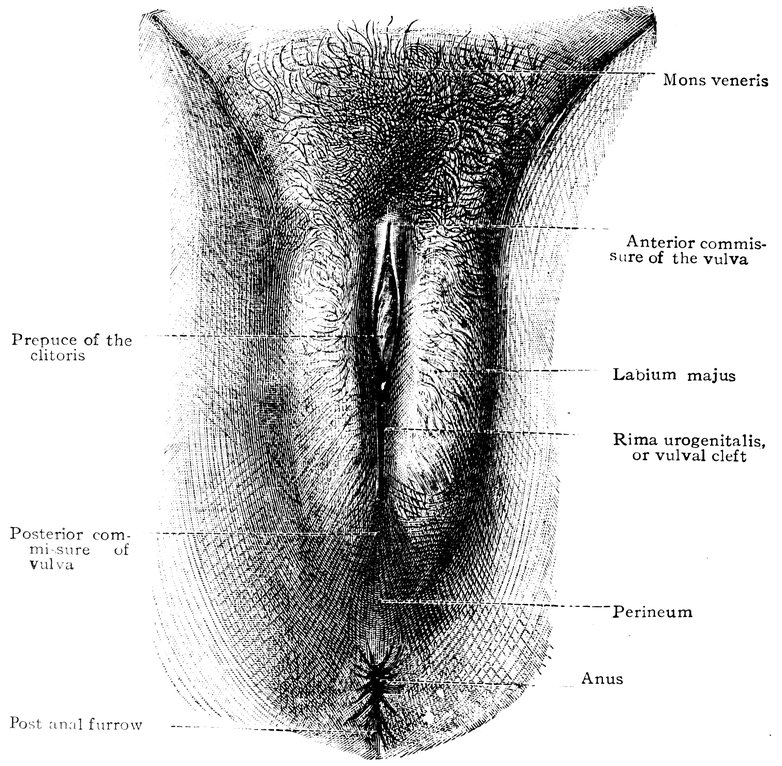

| 48. | The female pudendum, or vulva, with the labia majora | 204 |

| 51. | Female internal genital organs in the fully developed state | 208 |